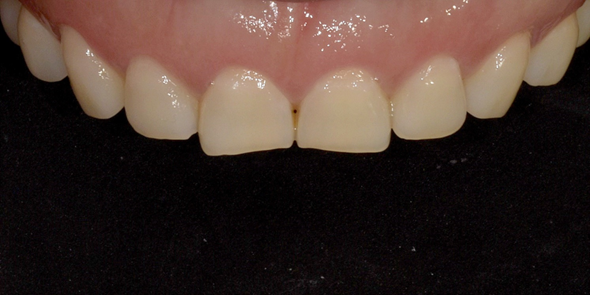

잇몸성형 시술 사례

(전) 2022-12-08 (후) 2022-12-22

특히나 저희 디데이치과의 경우 잇몸성형 1회 시술이 끝나고 2주 후에 리터치까지 진행해

개선된 잇몸라인이 더욱 더 확실하게 자리를 잡도록 도와드리고 있습니다.